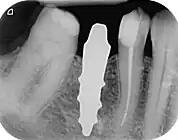

A new attempt was made by Pirker et al 2004 in a human trial with root analogue zirconia implants, but this time by applying differentiated osseoingration on the surface. In 2011 he reported 90% success rate with this method in a 2.5 year human trial.[16]

- 1 2 3 Pirker, W; Wiedemann, D; Lidauer, A; Kocher, A (2011). "Immediate, single stage, truly anatomic zirconia implant in lower molar replacement: a case report with 2.5 years follow-up". International Journal of Oral and Maxillofacial Surgery. 40 (2): 212–6. doi:10.1016/j.ijom.2010.08.003. PMID 20833511.